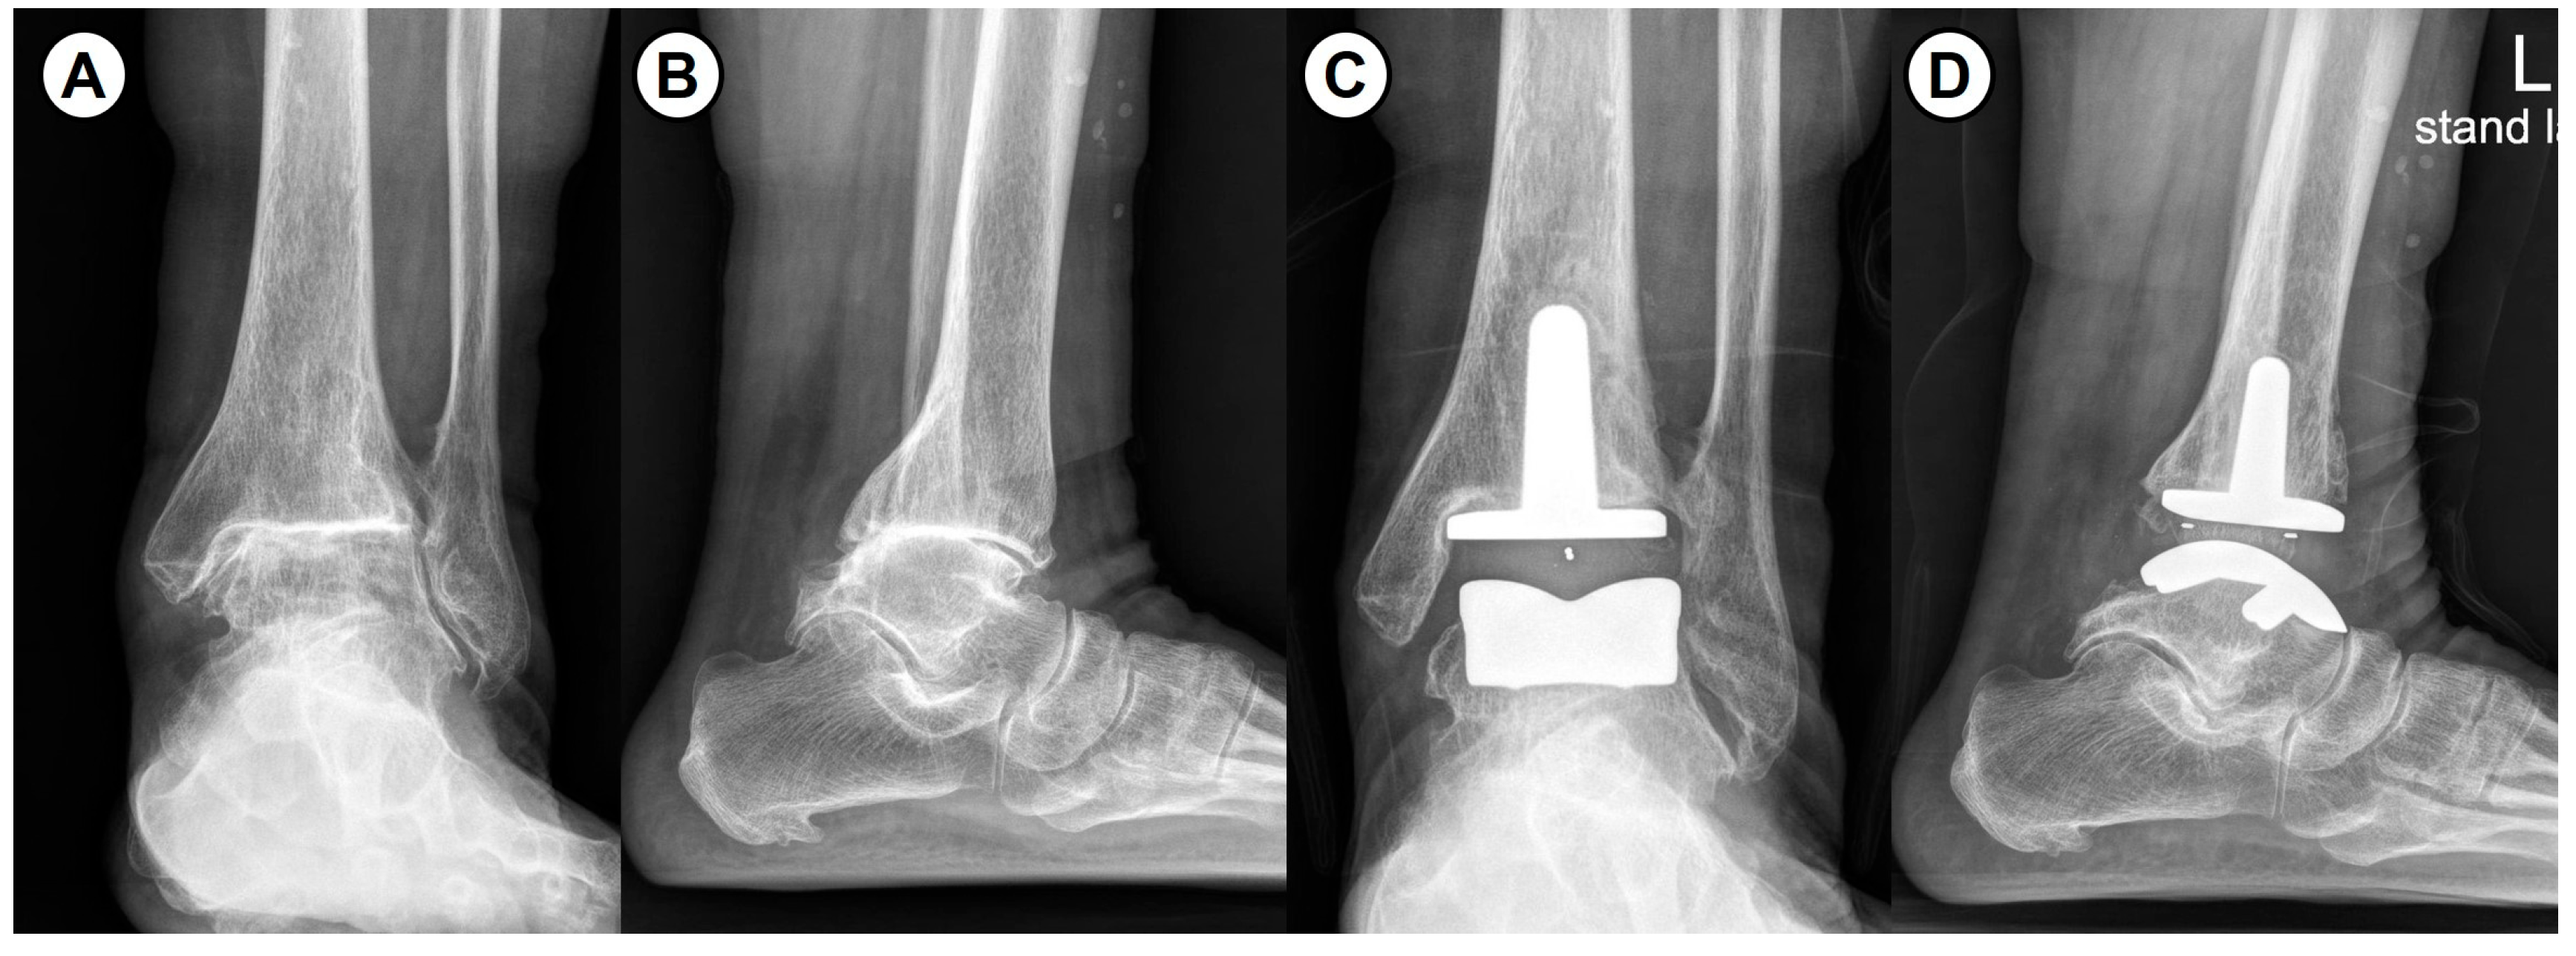

From January 2017 to June 2023, a total of 34 patients diagnosed with end-stage ankle RA who underwent TAA and were followed for 2 years were included in this study. A total of 16 patients without the modification of perioperative anti-rheumatic medications from January 2017 to April 2020 were classified into the uncontrolled group. Consecutively, 18 patients with the modification of perioperative anti-rheumatic medications from May 2020 to June 2023 were classified into the controlled group. All surgeries were performed by a single surgeon using a third-generation three-component mobile-bearing implant system (Zenith™; Corin, Cirencester, UK) (Figure 1 and Figure 2). The modification of perioperative anti-rheumatic medications was performed according to an established guideline [17] used in total hip and knee arthroplasty.

Figure 2. Intraoperative photograph showing the three-component mobile-bearing total ankle arthroplasty (Zenith™).